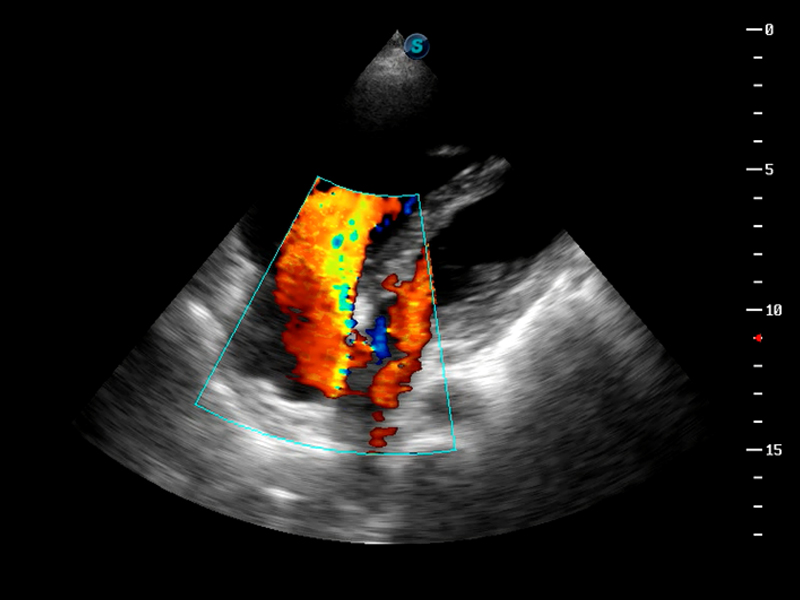

S9便携式彩色多普勒超声诊断仪是球速体育入口研发的高端便携彩超设备,外观设计新颖、产品性能卓越。S9在便携超声领域采用了突破传统的触摸屏交互设计,并以先进的软件硬件技术和设计理念,为您带来清晰的图像质量、稳定的工作性能和便捷的操作体验。

μ-Scan微米成像

AutoC智能血流追踪